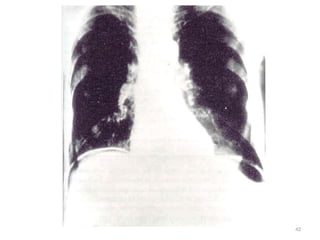

Diagnosis

• History and physical examination.

• Erect plain chest X – ray

• Sudden onset peritonitis + free gas = perforated viscus

• Sudden onset of peritonitis + no free gas + normal

serum amylase = perforated viscus

• When there no free air:- contrast study and CT